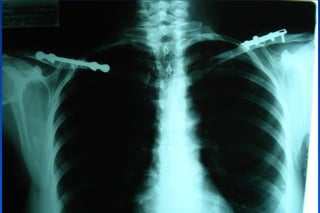

Fx Clavícula

Fx Clavicula: Criterios quirúrgicos

✓Fx abiertas

✓Hombro flotante

✓Pseudoartrosis

✓Interposicion de partes blandas

✓Compromiso neurovascular

✓Compromiso pleuropulmonar